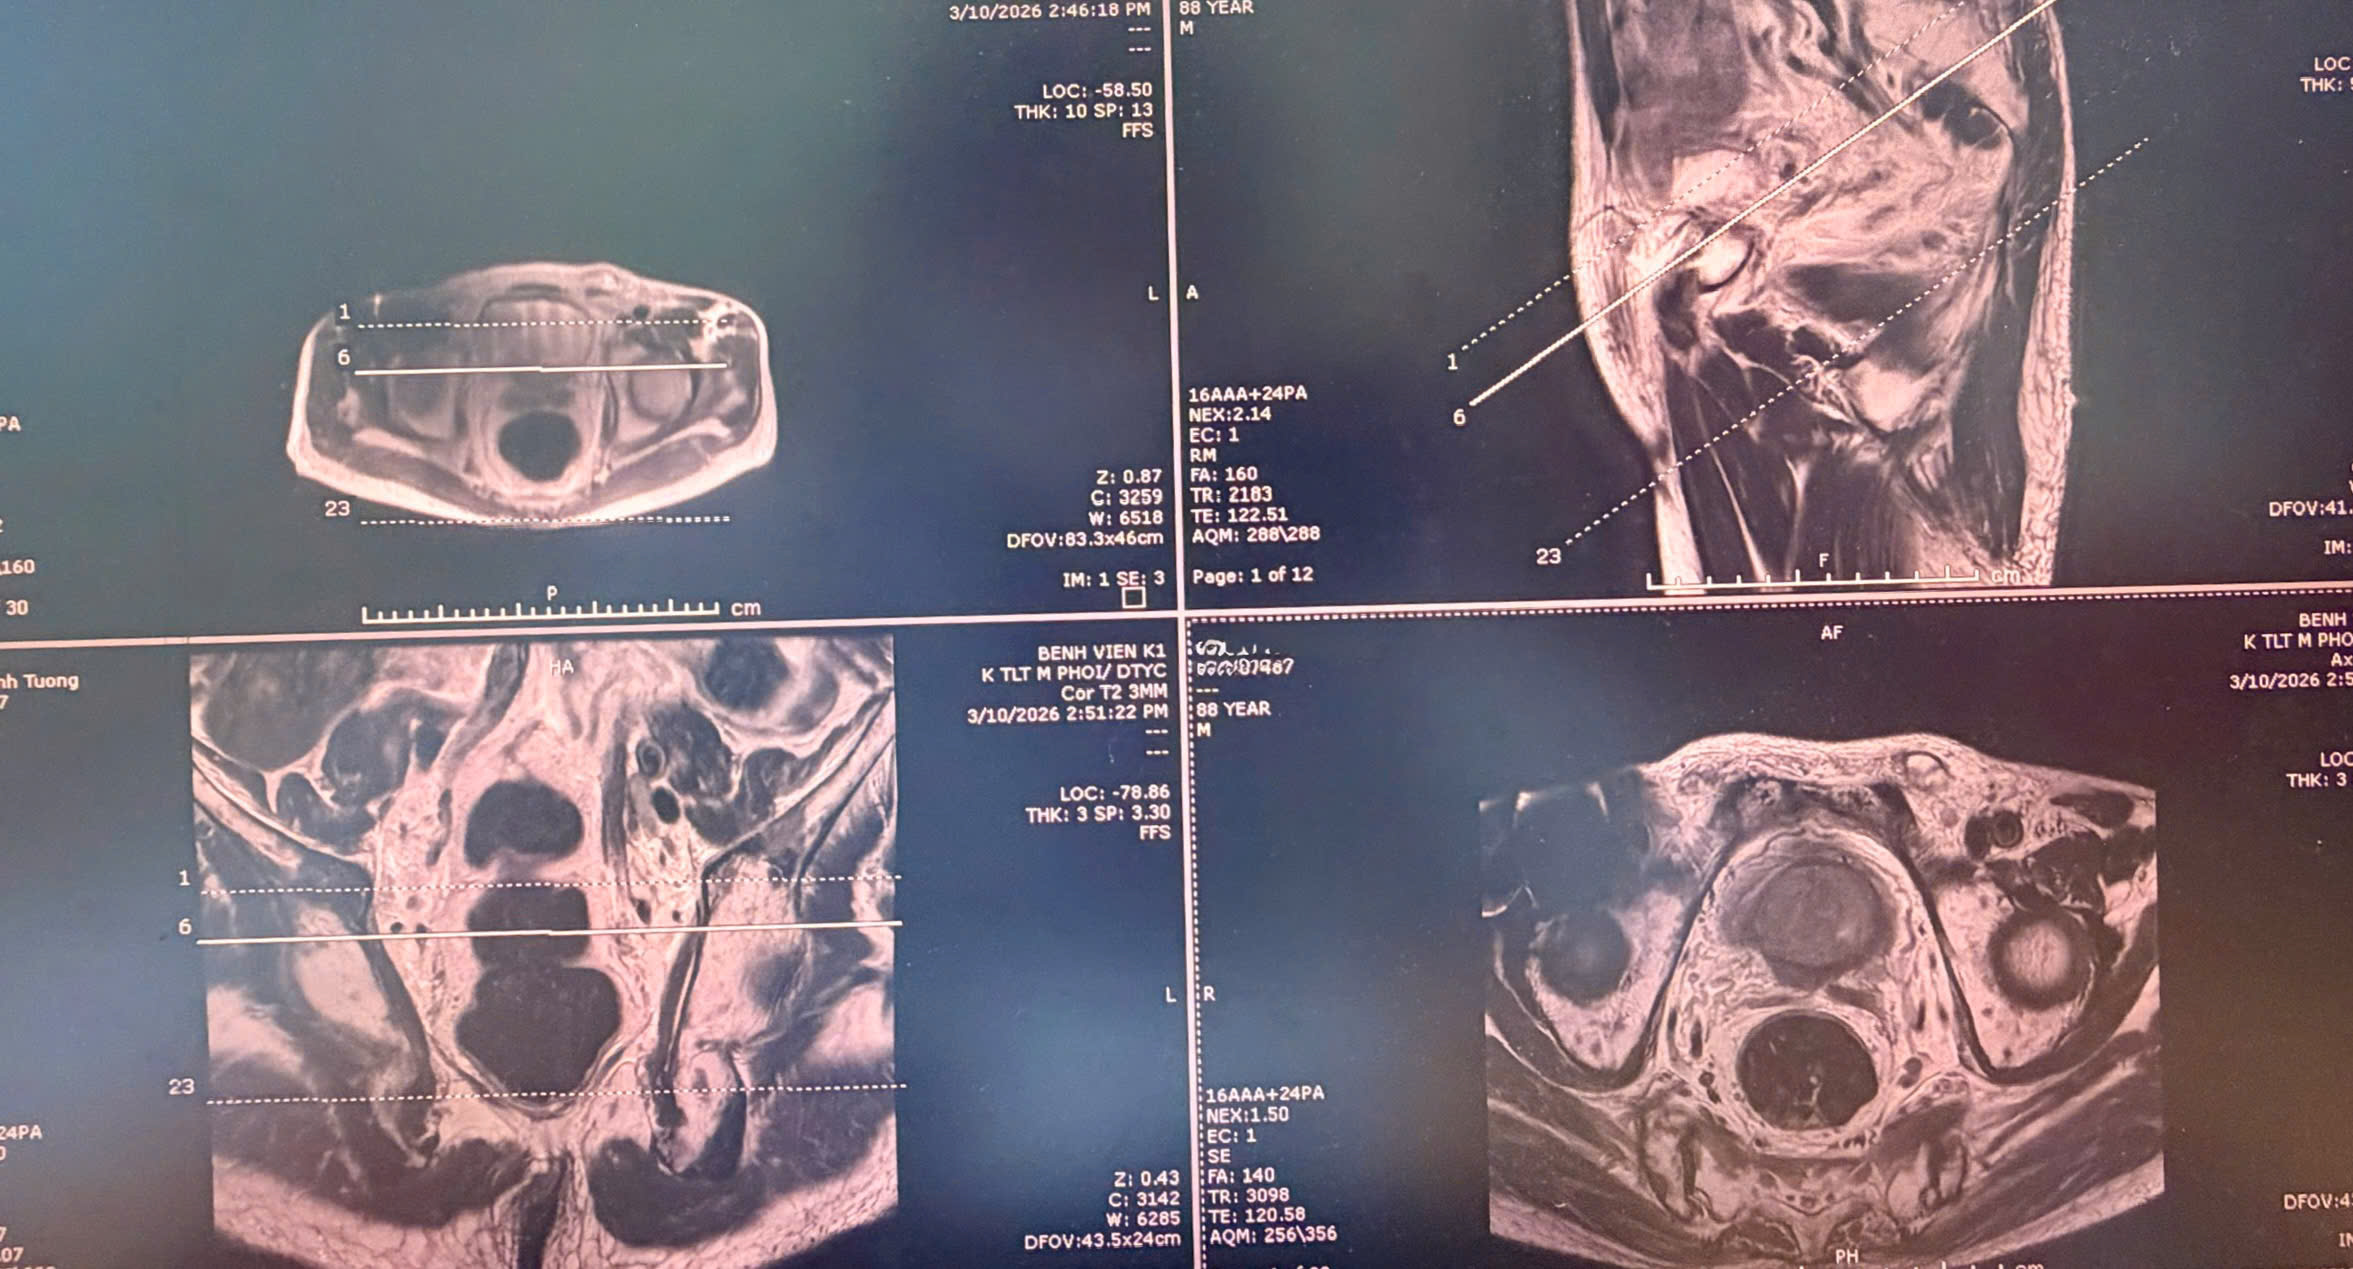

Hình ảnh chụp cộng hưởng từ chuyên sâu cho thấy các tổn thương của của bệnh nhân

Thực hiện kĩ thuật chụp cộng hưởng từ chuyên sâu cho ung thư tiền liệt tuyến (mpMRI – multiparametric MRI) cho thấy, tuyến tiền liệt kích thước khoảng 49×46×37mm, thể tích tương đương ~43cm³. Tổn thương vùng ngoại vi phía sau lệch trái kích thước 9×12mm, bờ không đều. Tổn thương xâm lấn túi tinh cùng bên, chưa phát hiện xâm lấn cấu trúc lân cận khác.

Từ đó, các bác sĩ đưa ra kết luận phân loại tổn thương PIRADS 5 – mức độ nghi ngờ ung thư rất cao. Ngoài ra, hình ảnh cũng cho thấy có các nốt bất thường tín hiệu rải rác tại xương chậu hai bên và xương cùng, dấy lên khả năng di căn xương. Thoát vị bẹn trái kích thước khoảng 25×15mm gây áp lực ổ bụng, cũng là yếu tố cần được xem xét trong quá trình điều trị.